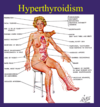

Mild hyperthryodiism

still dangerous

risk of a fib, tachycardia, APBs, reduced bone density

esp in elderly